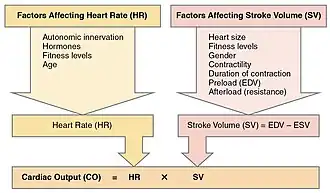

Cardiac output is a global blood flow parameter of interest in hemodynamics, the study of the flow of blood. The factors affecting stroke volume and heart rate also affect cardiac output. The figure at the right margin illustrates this dependency and lists some of these factors. A detailed hierarchical illustration is provided in a subsequent figure.

From this formula, it is clear the factors affecting stroke volume and heart rate also affect cardiac output. The figure to the right illustrates this dependency and lists a few of these factors. A more detailed hierarchical illustration is provided in a subsequent figure.

Equation (1) reveals HR and SV to be the primary determinants of cardiac output Q. A detailed representation of these factors is illustrated in the figure to the right. The primary factors that influence HR are autonomic innervation plus endocrine control. Environmental factors, such as electrolytes, metabolic products, and temperature are not shown. The determinants of SV during the cardiac cycle are the contractility of the heart muscle, the degree of preload of myocardial distention prior to shortening and the afterload during ejection.[70] Other factors such as electrolytes may be classified as either positive or negative inotropic agents.[71]